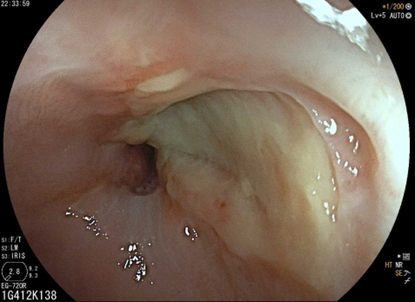

Depuis un an, elle rapporte des crampes d’estomac, notamment après des repas copieux, évoluant par périodes, ainsi qu’un pyrosis nocturne plusieurs fois par semaine. Elle a remarqué dernièrement une gêne thoracique lorsqu’elle boit de l’alcool et lors de ses séances de sport. Il n’y a pas de troubles du transit.

Le pyrosis et le syndrome postural sont des signes typiques de RGO.